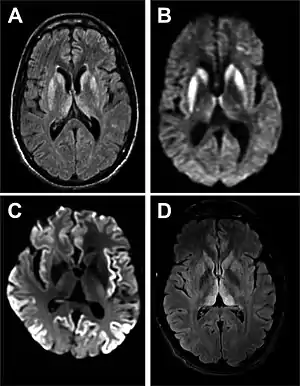

Imaging of the brain may be performed during medical evaluation, both to rule out other causes and to obtain supportive evidence for diagnosis. Imaging findings are variable in their appearance, and also variable in sensitivity and specificity.[41] While imaging plays a lesser role in diagnosis of CJD,[42] characteristic findings on brain MRI in some cases may precede onset of clinical manifestations.[43]

Brain MRI is the most useful imaging modality for changes related to CJD. Of the MRI sequences, diffuse-weighted imaging sequences are most sensitive. Characteristic findings are as follows:

- Focal or diffuse diffusion-restriction involving the cerebral cortex and/or basal ganglia. In about 24% of cases DWI shows only cortical hyperintensity; in 68%, cortical and subcortical abnormalities; and in 5%, only subcortical anomalies.[44] The most iconic and striking cortical abnormality has been called "cortical ribboning" or "cortical ribbon sign" due to hyperintensities resembling ribbons appearing in the cortex on MRI.[45] The involvement of the thalamus can be found in sCJD, is even stronger and constant in vCJD.[46]

- Varying degree of symmetric T2 hyperintense signal changes in the basal ganglia (i.e., caudate and putamen), and to a lesser extent globus pallidus and occipital cortex.[42]

| Signal hyperintensity in the caudate nucleus and putamen on diffusion-weighted and FLAIR MRI | Often present | Often absent |

| Pulvinar sign-bilateral high signal intensities on axial FLAIR MRI. Also posterior thalamic involvement on sagittal T2 sequences | Not reported | Present in >75% of cases |